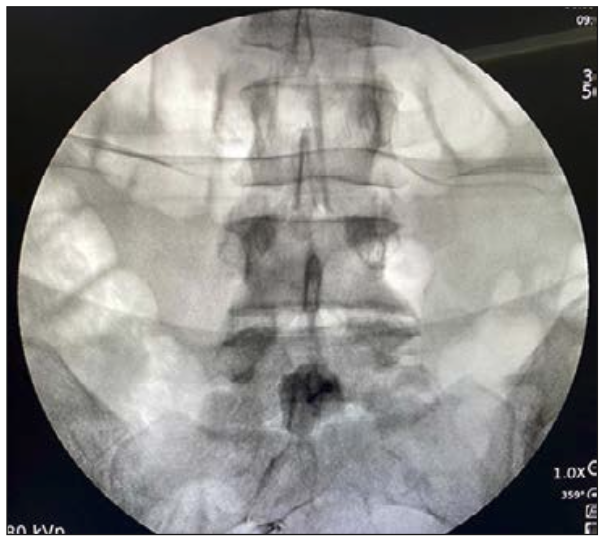

Reyad et al (38) comparó en un estudio la rizotomía química con la rizotomía termal. Cuarenta pacientes portadores de cáncer pélvico y con dolor perineal moderado o severo no controlado con dosis máximas de morfina durante al menos 4 semanas fueron asignados aleatoriamente para recibir rizotomía selectiva mediante ablación térmica por radiofrecuencia (80°C durante 180 segundos) de las raíces sacras S3 unilateral y ablación bilateral de S4 (n = 20), o rizotomía química convencional con fenol hiperbárico al 6% en glicerina (n = 20). Los pacientes fueron evaluados en la intensidad del dolor, el consumo diario de analgésicos, la mejoría funcional, la satisfacción general del paciente, el grado de discapacidad y la aparición de efectos secundarios relacionados con el procedimiento a las 1, 4 y 12 semanas. Los resultados fueron comparables en ambos grupos en cuanto al control del dolor y la mejoría funcional. Sin embargo, la incidencia de complicaciones mayores fue significativamente mayor en el grupo fenol (5 pacientes, 25%), entre ellas 4 pacientes desarrollaron disfunción vesical que requirió instalación de sonda vesical, 2 pacientes tuvieron incontinencia fecal y 1 paciente presentó paresia. En nuestra unidad preferimos la rizotomía termal unilateral en S3 y radiofrecuencia pulsada en la S3 contralateral, más ablación termal bilateral en S4 (Figura 7).

Figura 7: Se observan 4 cánulas de radiofrecuencia en S3 y S4 para realizar rizotomía termal unilateral en S3 y radiofrecuencia pulsada en la S3 contralateral, más rizotomía termal bilateral en S4.